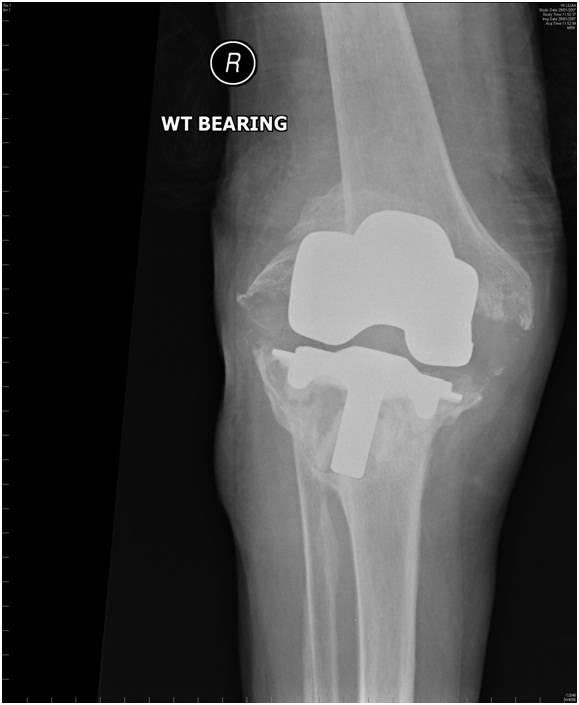

• Loosening or wear – with time a joint replacement may wear out or come loose. Your surgeon can to assess your knee together with an up-to-date Xray to determine if this has occurred.